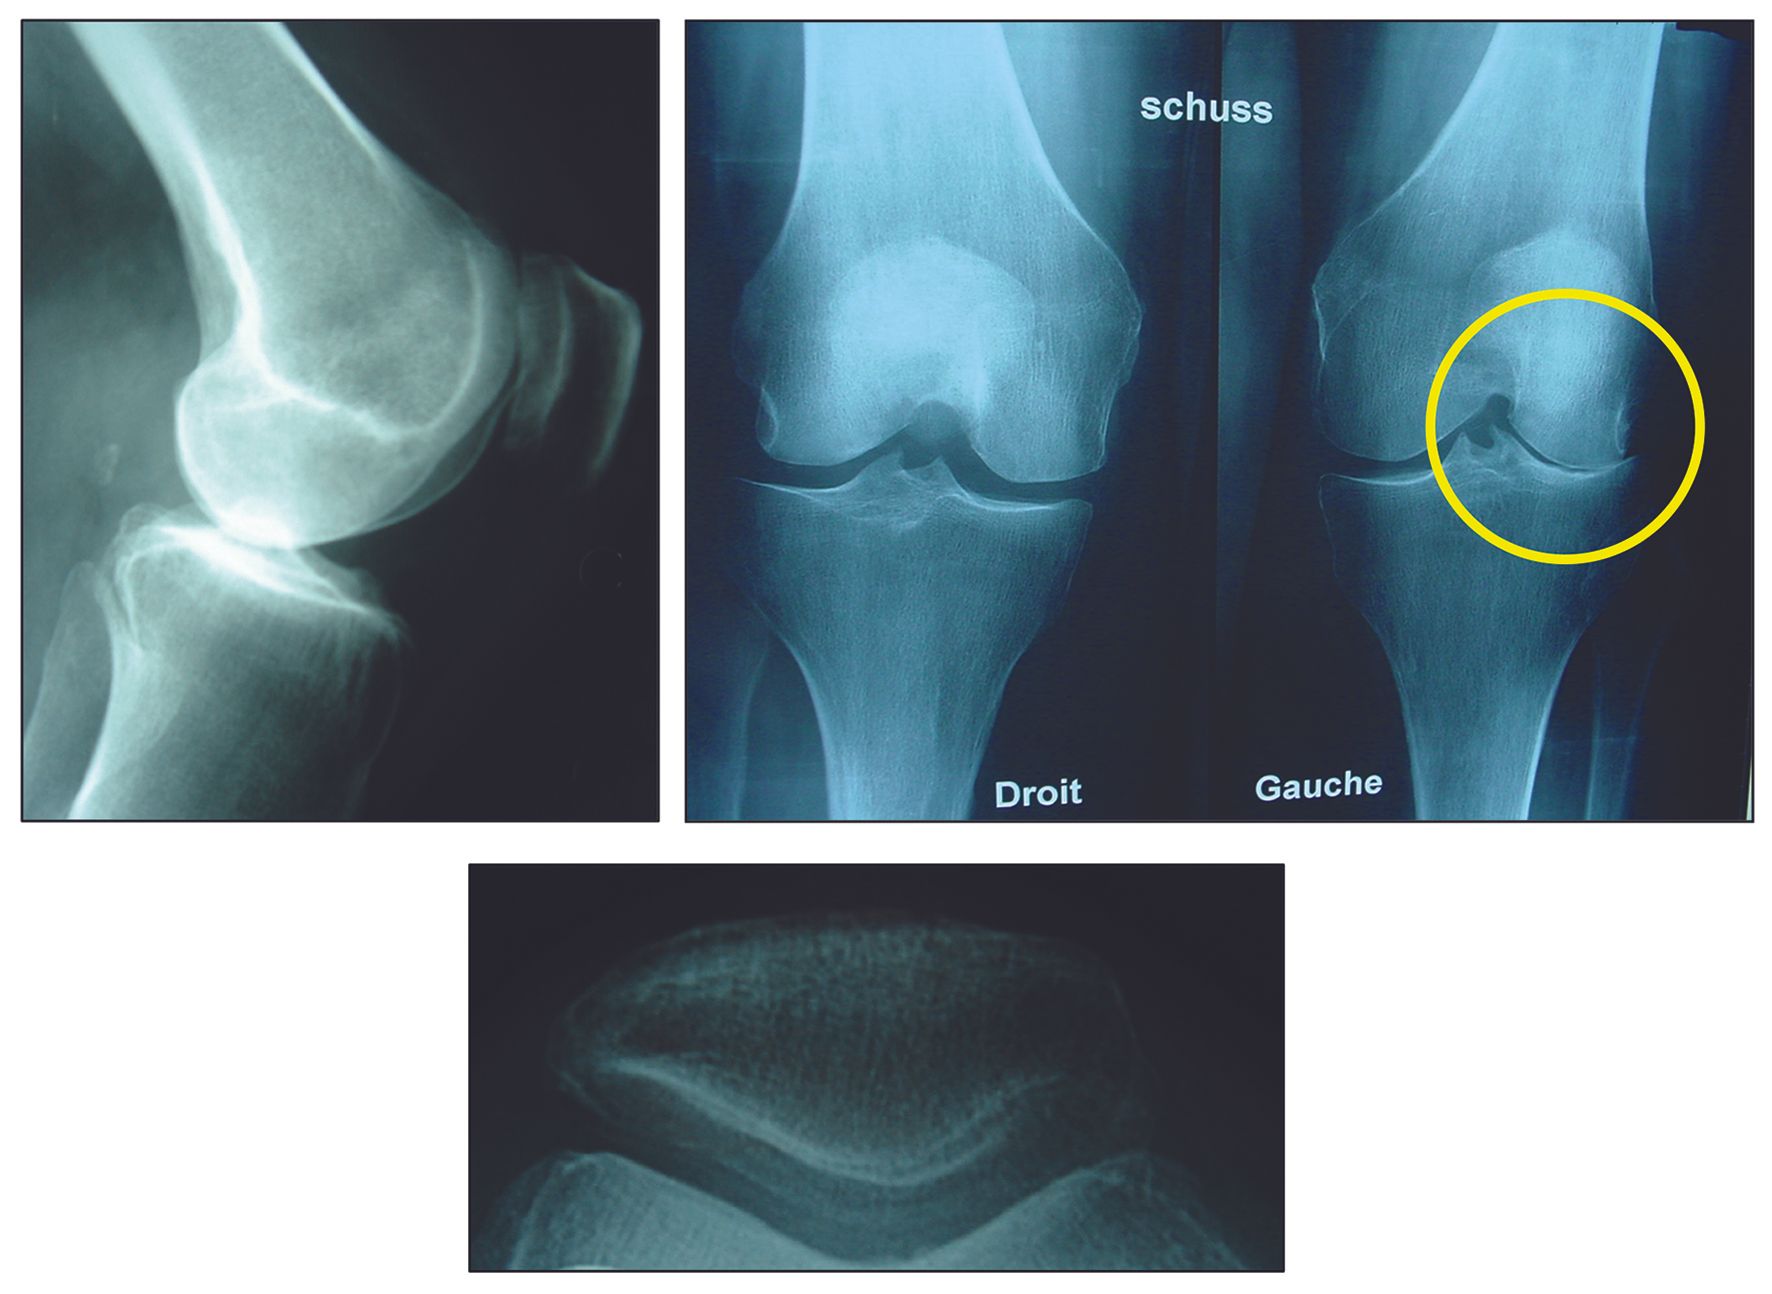

Isolated damage to the lateral tibiofemoral compartment is a determining factor for the indication. In some cases, the special 45° inclined PA view (Rosenberg or Lyon Schuss) will be necessary to identify the OA damage of the posterior femur condyle (Fig. 1). Local osteo-cartilage damage caused by spontaneous osteonecrosis (SPONK) of the lateral condyle is also a good indication (Fig. 2).